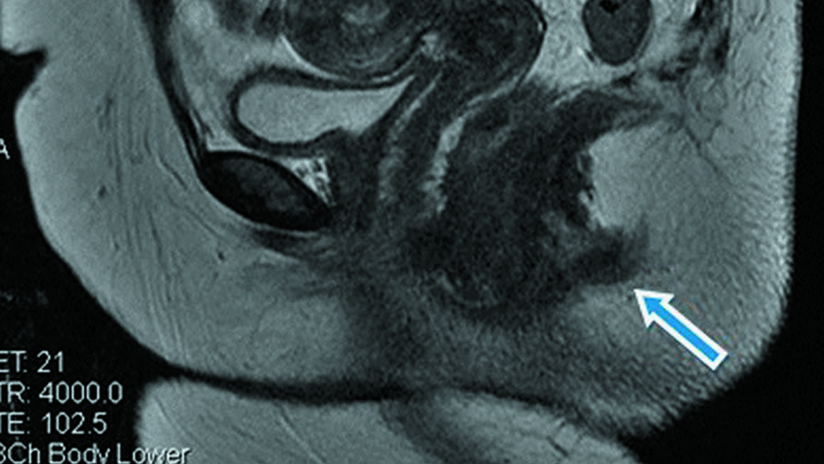

La paciente, cuya identidad no fue revelada, primero acudió a un chequeo médico pues tenía abscesos en la zona. Al pasar por las máquinas de resonancia, los especialistas confirmaron que tiene una “estructura tubular posterior al canal anal”.

Su segundo orificio fue descrito por los médicos como una cavidad de solo tres centímetros de profundidad y un centímetro de ancho que no está conectada a las paredes rectales.